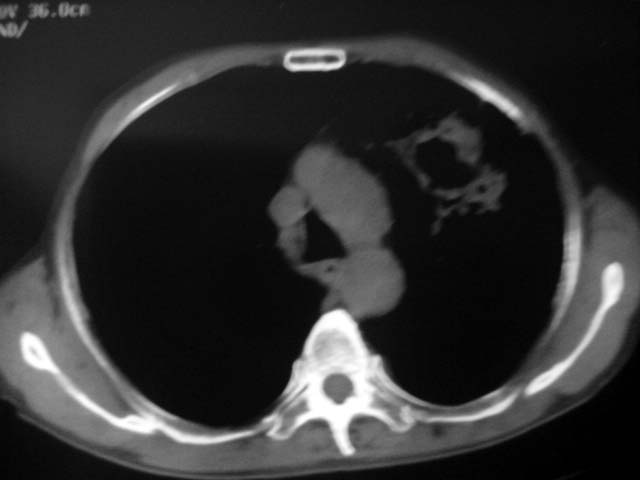

以下是引用zjzjr在2007-9-4 17:00:00的发言:[br]双上肺继发型结核伴左上肺空洞形成.慢性支气管炎伴肺气肿.

以下是引用liuzheng_9326在2007-9-4 16:23:00的发言:[br]痰检未见结核菌, 治疗后症状好转。图像符合陈旧性结核伴感染。